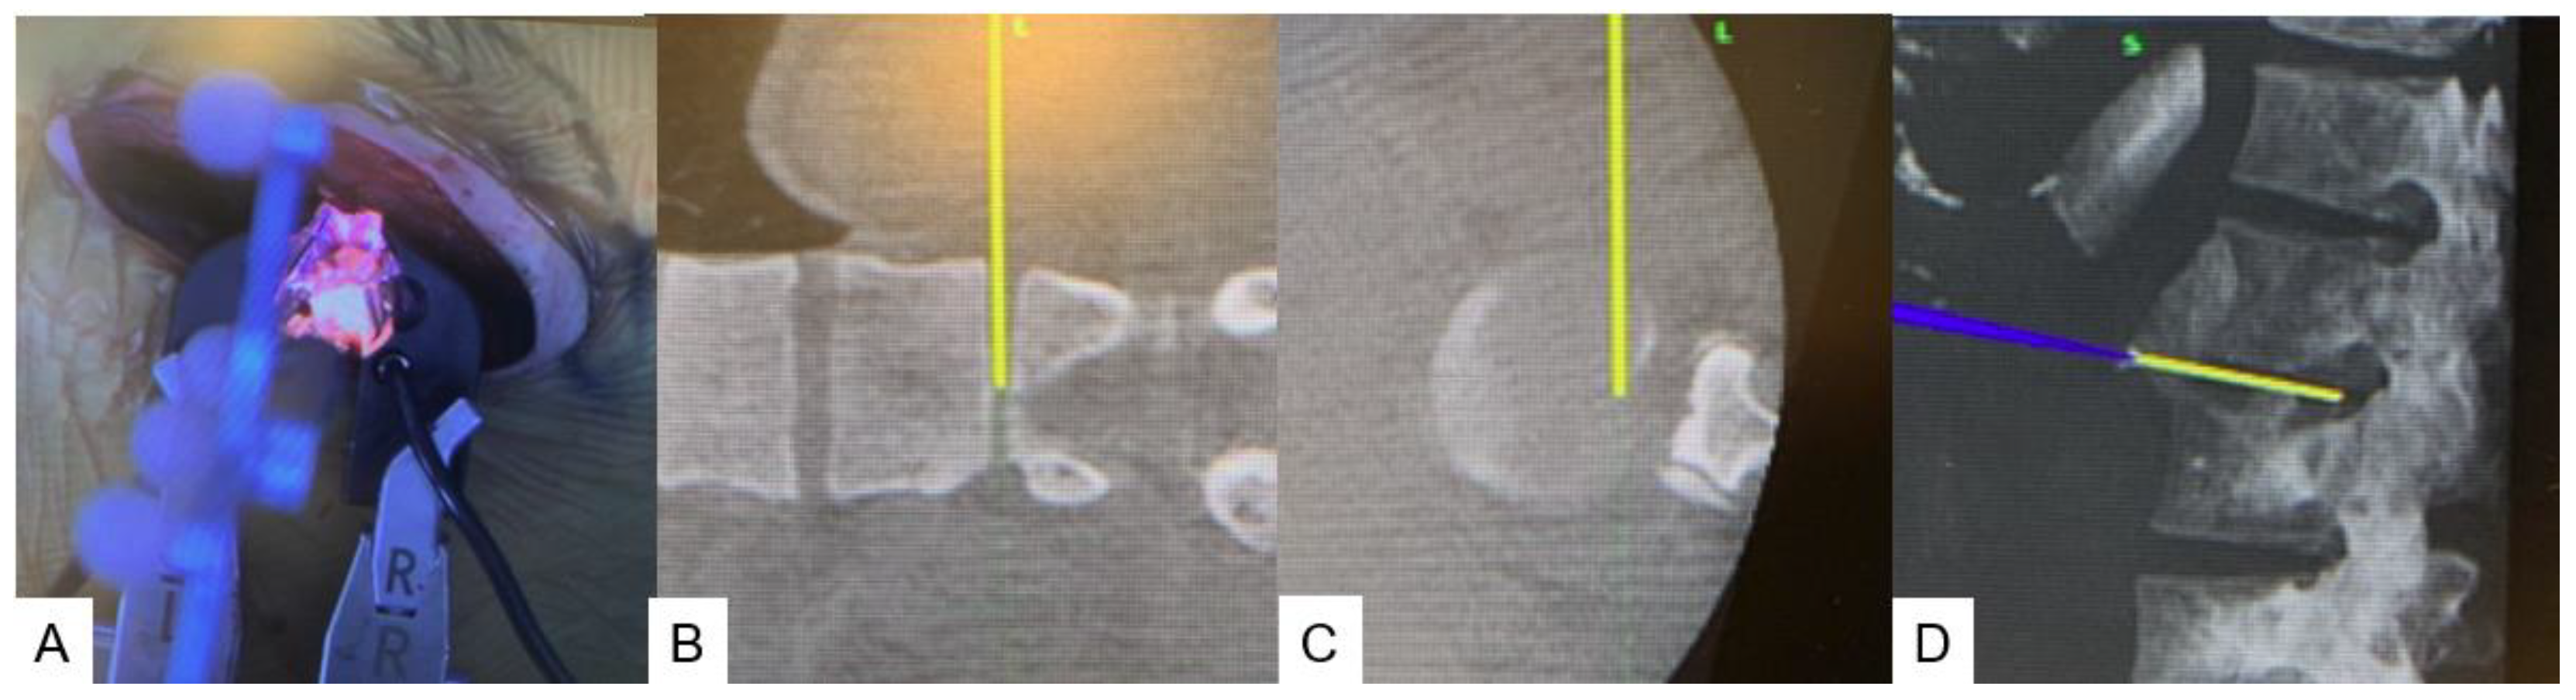

2.4. Surgery

2.4.1. Anterior disectomy

2.4.2. Posterior osteotomy